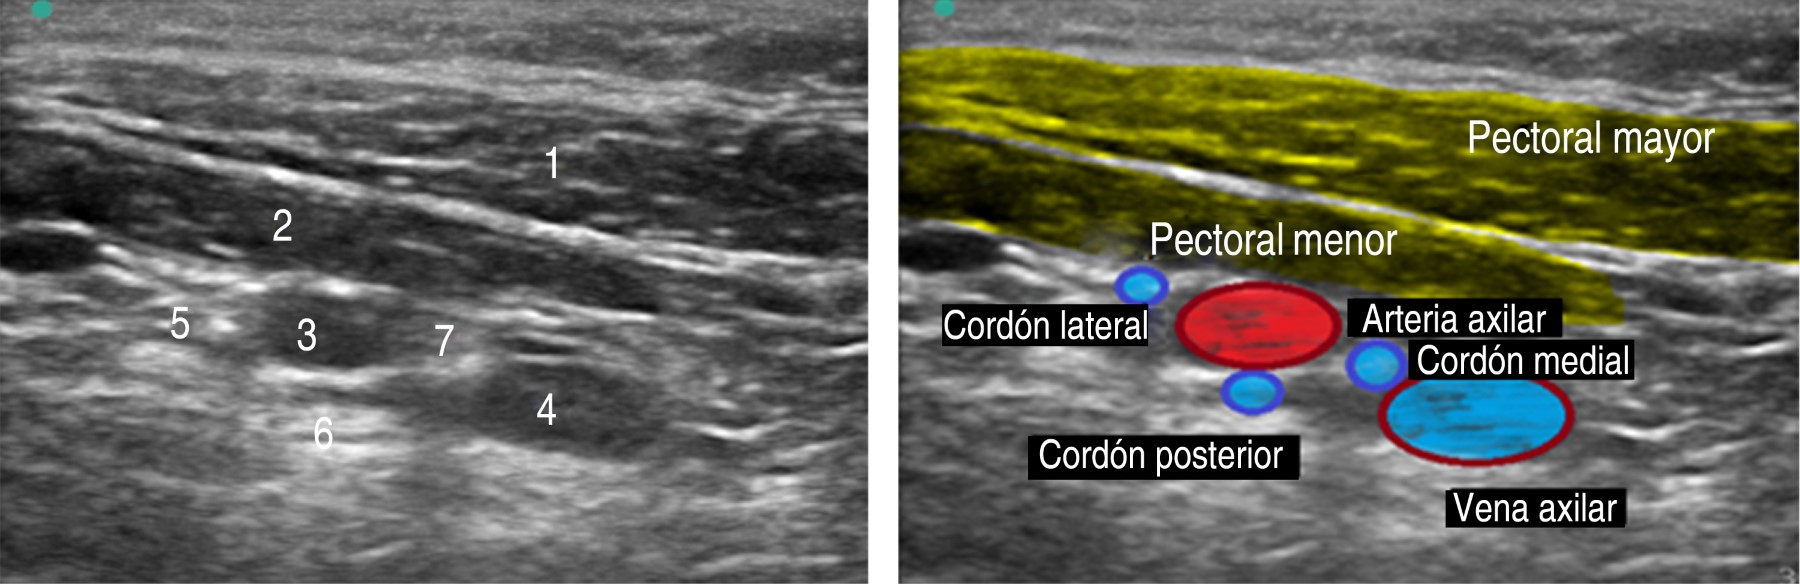

Effectiveness of brachial plexus block with costoclavicular approach and factors modifying sonoanatomy in pediatric patients

Pediatric brachial plexus block has become a good alternative for upper extremity surgical procedures, especially since the advent of ultrasonography. The main aim of the study was to evaluate the effectiveness of the blockade with the costoclavicular approach in the pediatric population, and compare the sonoanatomy of the costoclavicular window with the coracoid one, and determinate if the position of the arm has an impact on the ultrasound image. A total of eight patients with upper limb fractures were evaluated. Of the eight patients, five were male (62.5%), three female (37.5%) with a mean age of 8.8 years. Ultrasonographic screening was performed comparing the sonoanatomy of the costoclavicular and coracoid approaches, better observing the brachial plexus cords and vascular structures with the costoclavicular approach. With the arm abducted 90 and 110o, a better visualization of the neurovascular structures and an improvement in the quality of the block was obtained. The ropivacaine dose was 1.5 mg/kg between 0.3-0.5%, with an average motor block time of 6.7 hours, and an average sensory block of 11.25 hours. There were not complications. In conclusion, the brachial plexus block via the costoclavicular approach in the pediatric population is a safe technique.

Figure 2